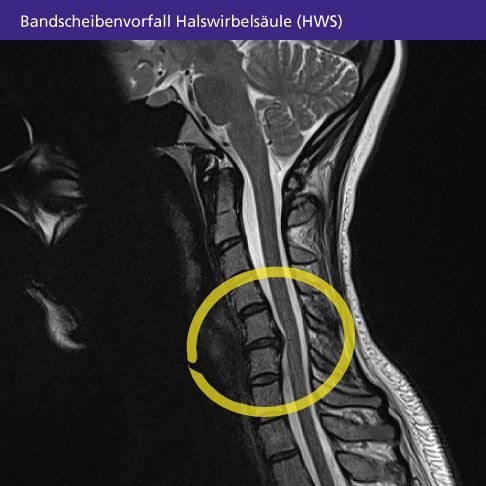

Bandscheibenvorfälle OHNE OP lösen !

Die einzig wahre und nicht invasive Alternative zur oftmals risikoreichen Wirbelsäulenchirurgie - Bandscheibenvorfälle,

Stenosen und sämtliche Rückenbeschwerden ohne OP, Spritzen und Infiltrationen sowie langen Wartezeiten wieder zu beheben!

Durch gezielten Zug auf die umgebenden Strukturen des betroffenen Wirbelsäulen-Abschnitts bekommt die Bandscheibe wieder mehr

Platz und entlastet somit den Druck auf den Spinalnerv - Auch bei HWS-Vorfällen sehr hilfreich, selbst bei Migräne und Schwindel

sowie Schleudertrauma, Cervicalsyndrom oder Nacken- u. Schulterverspannungen gut einsetzbar !

Lassen Sie die Bilder auf sich wirken - auch beim MRT ist zu erkennen dass sich ein Bandscheibenvorfall nach mehreren Sitzungen

deutlich zurückbilden kann!